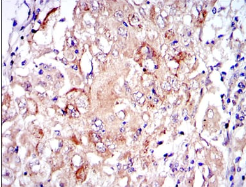

IHC    1/200 - 1/1000